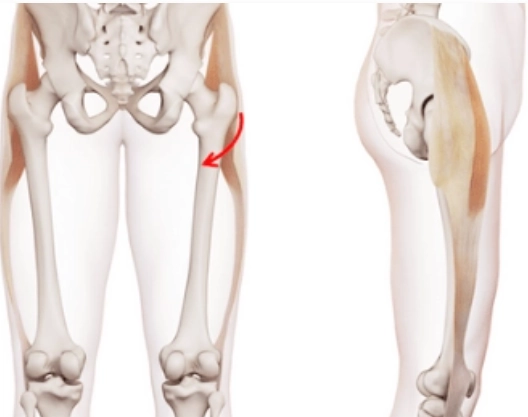

Tổn thương cơ khép dài (Adductor longus)(nhóm cơ khép háng)

16/03/2026